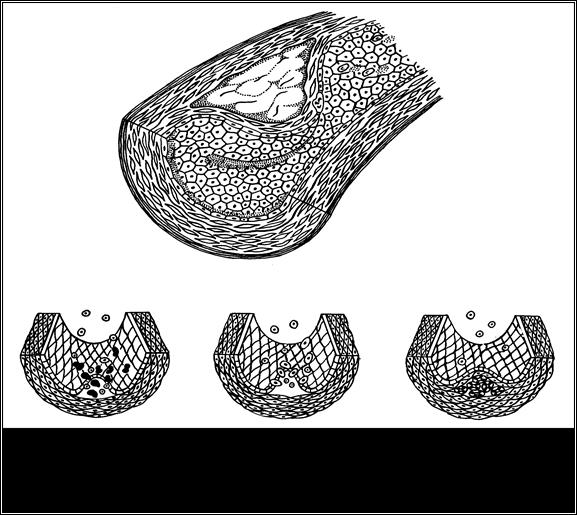

Стадии развития атеросклероза

Рис.18

Обозначения: 1,2. Обратимые стадии атеросклероза. 3,4,5. Необратимые стадии атеросклероза

Тип I (стадия начальных поражений) характеризуется неспецифическими долипидными изменениями в интиме сосудов, вызванными любыми экзогенными и эндогенными факторами альтерации. Внешне они проявляются разрыхлением и истончением защитного гликокаликса на поверхности эндотелиоцитов, расширением межэндотелиальных щелей, накоплением в интиме гидрофильных гликозаминогликанов и ее отеком. Над участками измененного эндотелия формируются пристеночные агрегаты моноцитов и тромбоцитов. Подобные долипидные изменения интимы обнаруживаются даже в артериях годовалых детей.

Тип II (стадия липидных пятен и полосок) характеризуется миграцией моноцитов в интиму и нарастающей ее инфильтрацией ЛПНП и ЛПОНП – процессами, инициированными эндотелиальными и моноцитарными цитокинами. Цитокины – пероксиды активируют процессы ПОЛ в эндотелиоцитах и миоцитах медии. Цитокины – хемоаттрактанты (ИЛ-1, ФНОα и моноцитарный хемотактический белок I) рекрутируют в интиму из крови все новые моноциты и тромбоциты, а тромбоцитарный фактор роста (ТФР) стимулирует миграцию в нее миоцитов из медии. В интиме липопротеины взаимодействуют с продуктом ПОЛ - малоновым диальдегидом, ацетилируются и усиленно захватываются «мусорными» рецепторами макрофагов и мигрирующими из медии гладкомышечными клетками. Насыщаясь атерогенными липопротеинами, они располагаются субэндотелиально и приобретают вид «вспененных» клеток – характерных элементов липидных пятен и полосок. Эта стадия очень часто встречается в артериях молодых людей (2 – 3 декады) и даже детей. Она обратима и не всегда прогрессирует.

Типы III (стадия липосклероза), IV (стадия атеромы) и V (стадия фиброатеромы и фиброзной бляшки) характеризуют необратимые изменения в прогрессе атеросклероза. Решающее значение в трансформации обратимых изменений в необратимые - имеют нарастающая продукция цитокинов и инфильтрация интимы атерогенными липопротеинами. Среди цитокинов приоритетную роль играют факторы роста: ИЛ-I, эндотелин I, тромбин, тромбоцитарные факторы роста гладких мышц, основной фактор роста фибробластов, фактор роста эпидермиса и др. Они стимулируют пролиферацию соответствующих клеток, а также биосинтез белков и гликозаминогликанов соединительной ткани миоцитами меди, которые накапливаются в сосудистой стенке. Липиды атеромы используются макрофагальной липооксигеназой для избыточного синтеза лейкотриенов, что вызывает локальный спазм сосуда и активирует в нем тромбообразование.

Морфологическими особенностями этих стадий атеросклеротического процесса являются:

♦- значительное скопление в интиме внеклеточных липидов и холестерина, формирующих на IV стадии липидное ядро атеромы;

♦- активная пролиферация и гибель «пенистых клеток, накопление межклеточного вещества в интиме и медии и формированием из него фиброзной «крышки» над ядром липидов. Так образуется фиброатероматозная или фиброзная бляшка (V стадия);

♦- сужение просвета артерий, выступающими в них атеросклеротическими бляшками.

Самые ранние сроки проявления III типа – третья декада жизни, IV типа - середина третьей декады, а V типа – начало четвертого десятилетия.

Тип VI (стадия осложненных поражений) характеризуется кальцификацией атеромы (атерокальцинозом), расщеплением или изъязвлением бляшки, наслаивающимся на нее тромбозом и финально - выраженной окклюзией сосуда и ишемией соответствующей области. Отрыв бляшки опасен липидной тромбоэмболией, а ее эволюция в медию может привести к образованию атеросклеротической аневризмы, разрыв которой в крупном сосуде (брюшная аорта) смертелен.